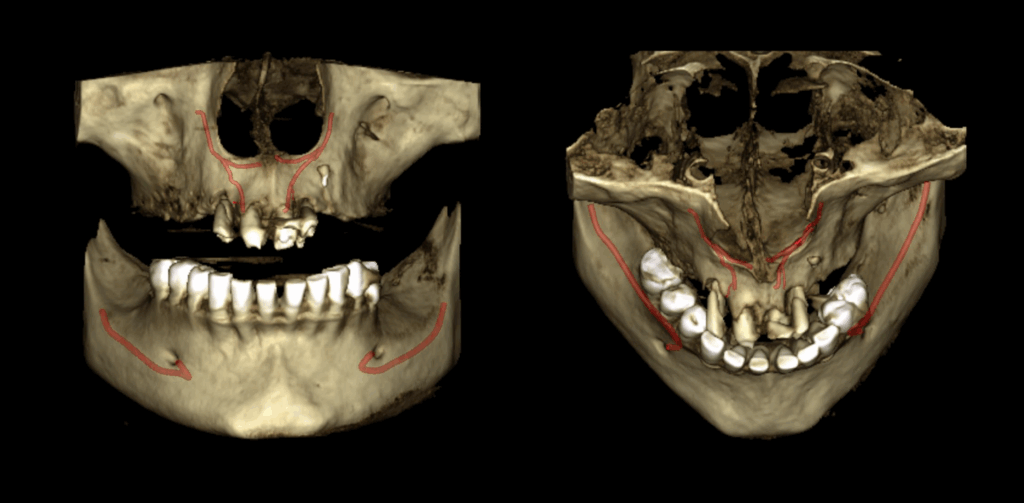

En el estudio complementario mediante tomografía computarizada de haz cónico (TCHC), se identifica la presencia del canalis sinuosus en el maxilar derecho, con trayecto que se dirige hacia la región ósea palatina correspondiente a las piezas 12 y 11. Asimismo, se evidencia un canalis sinuosus en el maxilar izquierdo, que se origina en la pared lateral de la fosa nasal izquierda y se dirige hacia la región ósea palatina y apical de las piezas 21 y 22.

Adicionalmente, se observa fractura radicular en la pieza 12, asociada a una imagen osteolítica periapical. Se identifican también fracturas radiculares con desplazamiento en las piezas 21 y 22. En la región correspondiente a la pieza 23, se evidencia un fragmento dentario sobre la cortical ósea vestibular.

RECONSTRUCCIÓN 3D